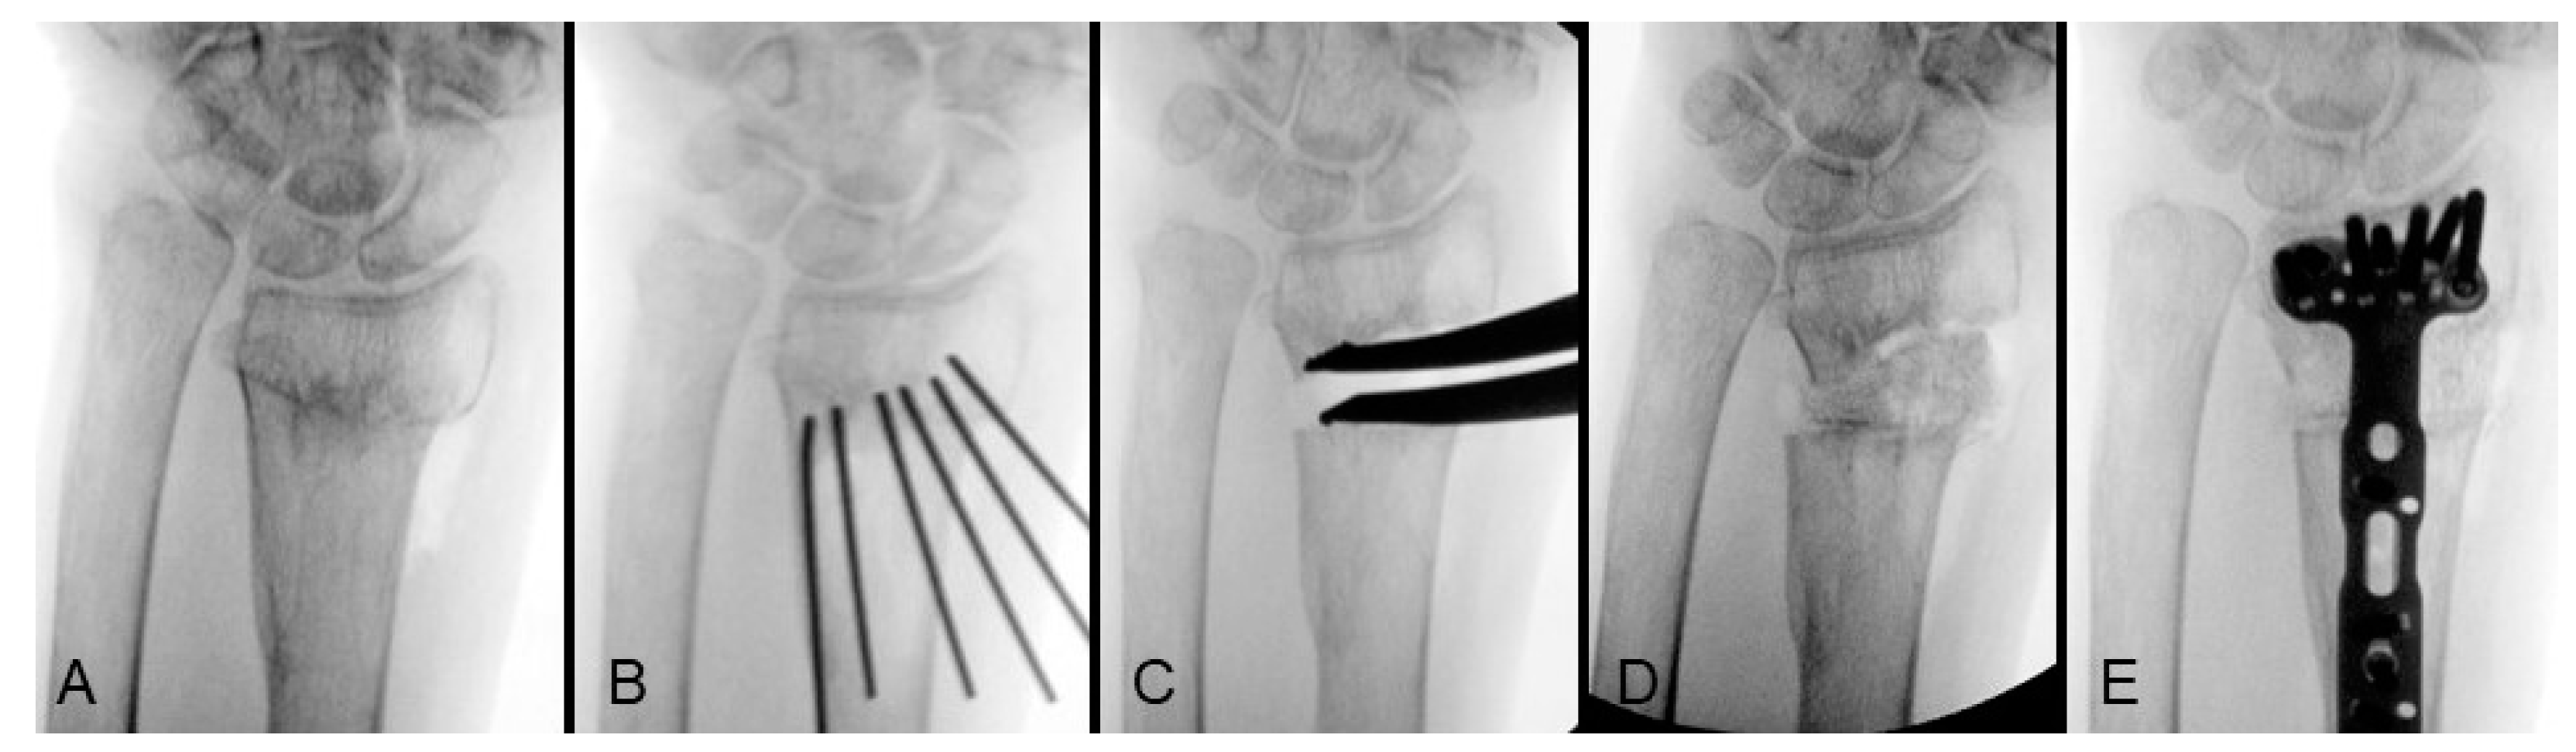

Tilt and Inclination

In cases with a relatively small osteotomy gap, intrafocal Kapandji K-wires are utilized to facilitate adjustments in alignment. One K-wire is placed dorsally to act as a lever for adjusting the volar tilt, while another intrafocal Kapandji K-wire is positioned radially to correct the radial inclination. However, if greater lengthening is required, resulting in a larger osteotomy gap, the lever effect of the Kapandji K-wire may diminish. In such cases, the distal fragment can be initially secured using the corresponding distal locking screws of a volar locking plate, utilizing the plate as a reduction template. By clamping the shaft end of the plate to the radial shaft, substantial correction of the volar tilt can be achieved even at large angles. Figure 2 illustrates the sequential process of tilt correction for an extra-articular distal radius malunion (Figure 2A). The osteotomy plane was initially formed by multiple K-wires (Figure 2B) and a defect was filled with allograft after radial height lengthening. An anatomical plate was used as a reduction template that the volar tilt was corrected by applying the subchondral articular locking screws first (Figure 2C), then clamping the plate to the shaft to rotate the articular fragment into the correct position (Figure 2D), and finally achieving definitive fixation by inserting all the remaining screws (Figure 2E).

Figure 2. Correction of tilt from extra-articular distal radius malunion: (A) preoperative lateral view; (B) osteotomy plane created by multiple K-wires; (C) allograft insertion and apply the articular locking screws of volar locking plate; (D) volar tilt corrected by clamping the plate to the radial shaft; (E) definitive fixation. Image courtesy of the corresponding author Chen-Yuan Yang, MD.